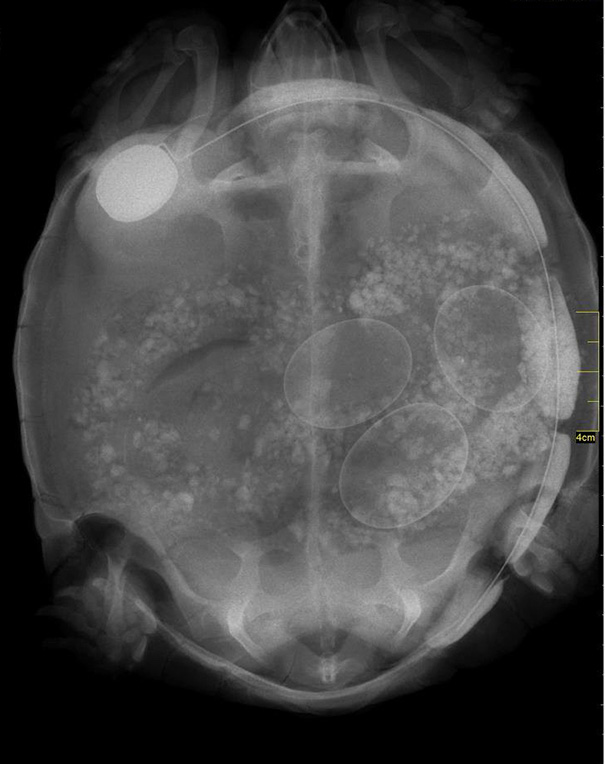

Unikāli rentgena attēli ar dzīvniekiem gaidībās

Bieži negadās publiski redzēt dzīvnieku rentgena uzņēmumus. Turklāt šie rentgena uzņēmumi ir veikti dzīvniekiem, kuri ir mazuļu gaidībās. Tagad ikvienam ir iespēja ielūkoties, kā dzīvnieku mazuļi attīstās savu mammu vēderos.